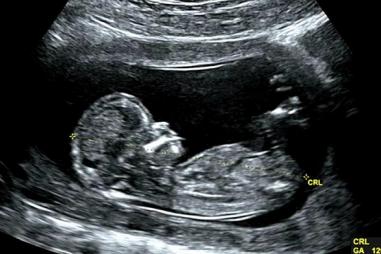

Poľsko: Pohrebná omša za 640 nenarodených detí

30.12.2020 PL

Rakvy obsahovali telá detí, ktoré zomreli pri spontánnych potratoch a interrupciách.  VARŠAVA, Poľsko - Katolícky biskup viedol pohrebnú omšu za 640 nenarodených detí.  Biskup Kazimierz Gurda z…